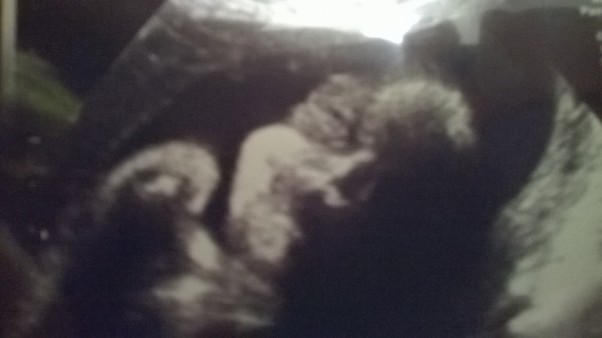

Wczoraj miałam usg. Nistety moi chłopcy nie mogli mi towarzyszyć jak to było zaplanowane, ale jeszcze trochę czasu zostało więc myślę, że nadrobimy. Z drugiej strony to tak już jest, że życie samo weryfikuje nasze plany. Synuś waży 1100 g i wszystko jest w porządku, a ja w końcu otrzymałam prezent od synka bo pokazał swojego buziaczka, na wcześniejszych badaniach pan doktor oczywiście wszystkich niezbędnych pomiarów dokonywał, ale żeby mama mogła nacieszyć oko, to synek płatał figla i się odwracał.

A teraz proszę, nawet udało się uchwycić na zdjęciu jego śliczną buźkę....